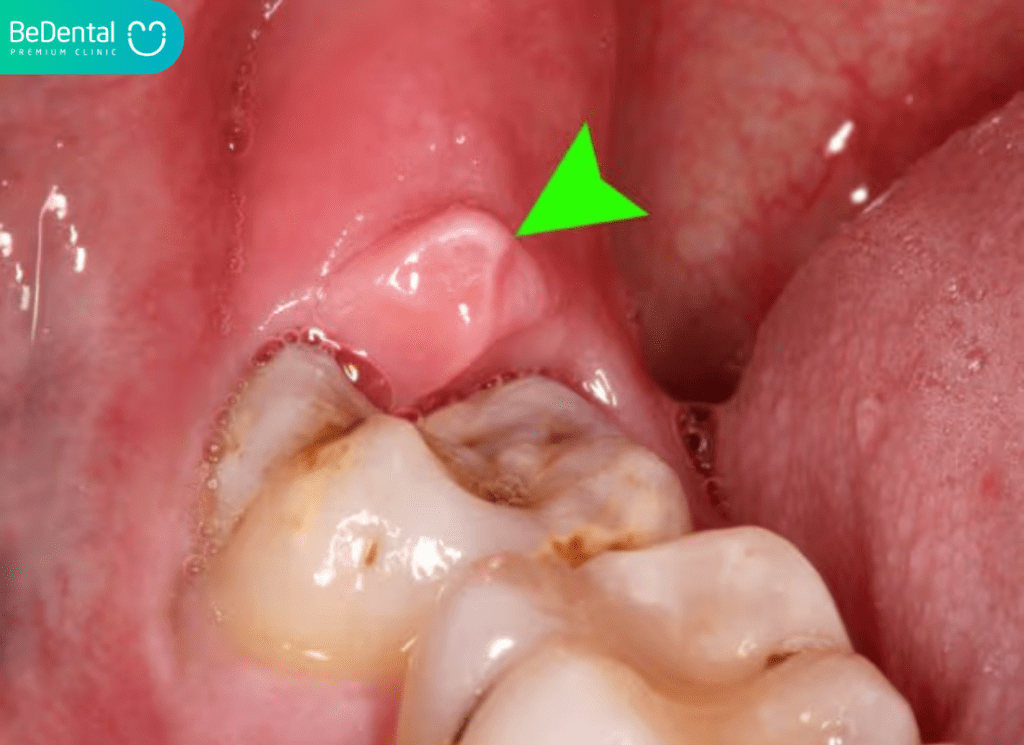

Lợi trùm là gì? Viêm lợi trùm răng khôn là tình trạng một vạt nướu (lợi) sưng tấy, che phủ lên một phần hoặc toàn bộ bề mặt răng khôn (răng hàm lớn thứ ba) chưa mọc hoàn toàn.

Quá trình mọc răng khôn diễn ra chậm và thường gặp khó khăn do thiếu không gian. Khi lợi trùm lên răng, nó tạo thành một khoảng trống nhỏ, kín đáo gọi là túi lợi.

Đây chính là môi trường lý tưởng để mảnh vụn thức ăn và vi khuẩn trú ngụ, sinh sôi, gây ra nhiễm trùng và dẫn đến hiện tượng viêm lợi trùm răng hàm dưới hoặc hàm trên. Tình trạng này còn được gọi là răng lợi trùm hoặc lợi trùm răng.